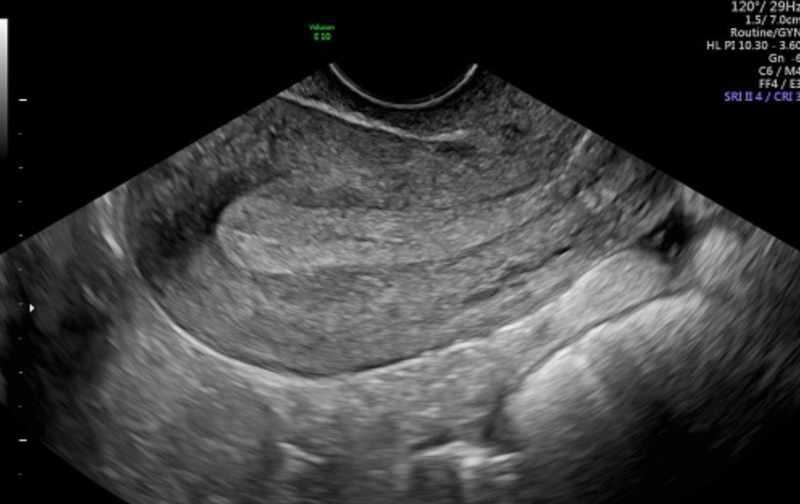

Vào khoảng tuần thứ 6 sau khi sinh mổ, các bà mẹ nên đi khám sức khỏe để bác sĩ kiểm tra khả năng lành vết mổ hoàn toàn. Trong lần tái khám này, bác sĩ có thể đề nghị siêu âm vết mổ sau sinh để đo chính xác độ dày tại vị trí vết mổ, mục đích là để đảm bảo quá trình phục hồi đang diễn ra đúng hướng và không có biến chứng.

Sau mổ lấy thai, cơ tử cung trải qua những thay đổi liên tục tại vị trí sẹo, tạo thành một hình tam giác trống phía trước cơ tử cung. Sự thay đổi về mặt giải phẫu này góp phần làm tích tụ chất lỏng ở vết thương mổ lấy thai cũ và tích tụ trong khoang tử cung, dẫn đến tình trạng gọi là tụ dịch vết mổ tử cung.

Tụ dịch vết mổ tử cung biểu hiện dưới dạng một lớp dịch tích tụ ở eo thành trước tử cung, đặc biệt ở vị trí vết sẹo mổ lấy thai cũ. Tình trạng này có thể gây chảy máu kéo dài và gây khó khăn cho việc thụ thai, ảnh hưởng đến sức khỏe sinh sản của chị em sau đó.

Việc xác định tụ dịch vết mổ tử cung khá khó khăn vì chị em thường không nhận biết được bất kỳ dấu hiệu cụ thể nào. Chỉ đến khi tình cờ siêu âm phụ khoa mới phát hiện có sự tích tụ chất lỏng. Tuy nhiên, vẫn có thể có một số dấu hiệu tiềm ẩn bao gồm chảy máu không rõ nguyên nhân, khó thụ thai và khó chịu dai dẳng ở vùng sẹo mổ lấy thai để chị em đi thăm khám sớm.